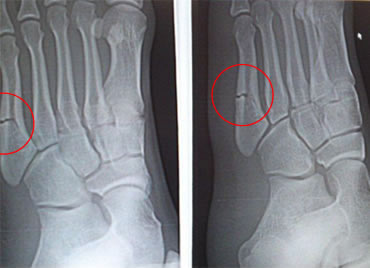

14歳(中学生/バスケットボール選手)男性 症状:中足骨骨折 (酸素カプセル)

回復の経過

酸素カプセル利用経過 2月26日 スタート時

酸素カプセル利用経過 3月19日 初期

酸素カプセル利用経過 4月9日 中期

酸素カプセル利用 4月23日 終了